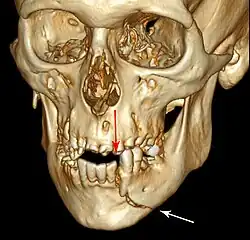

| 3D computed tomographic image of a mandible fracture in two places. One is a displaced right angle fracture and the other is a left parasymphyseal fracture. | |

Computed tomography is the most sensitive and specific of the imaging techniques. The facial bones can be visualized as slices through the skeletal in either the axial, coronal or sagittal planes. Images can be reconstructed into a 3-dimensional view, to give a better sense of the displacement of various fragments. 3D reconstruction, however, can mask smaller fractures owing to volume averaging, scatter artifact and surrounding structures simply blocking the view of underlying areas.

3D CT reconstruction of mandible fracture, white arrow marks fracture, red arrow marks moderate displacement and open bite -